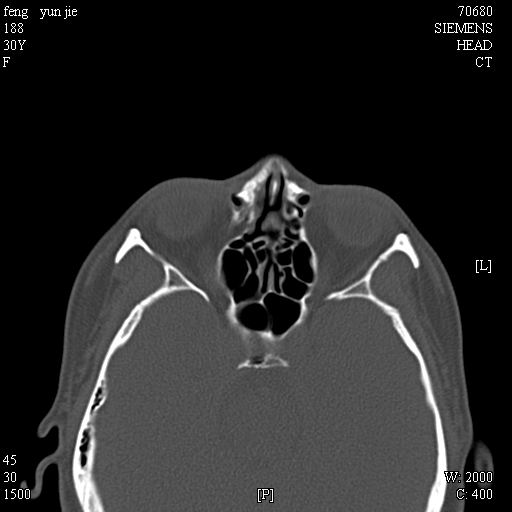

女,37岁,多年前鼻骨骨折过,现在穿刺有炎性分泌物

1)左侧鼻骨骨折(陈旧性)。2)双侧额窦及双侧筛窦炎症,伴右侧额筛窦黏液囊肿突入右侧眼眶。

考虑额窦粘液囊肿可能性大。

是黏液囊状还是淋巴瘤?建议结合穿刺细胞学检查。